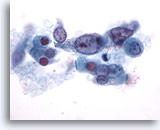

Figure 77

Sputum

Atypical squamous metaplastic cells are considered suspicious for squamous cell carcinoma as their nuclei become hyperchromatic and angulated. 60X

Sputum

Atypical squamous metaplastic cells are considered suspicious for squamous cell carcinoma as their nuclei become hyperchromatic and angulated. 60X

Figure 77

Sputum

Atypical squamous metaplastic cells are considered suspicious for squamous cell carcinoma as their nuclei become hyperchromatic and angulated.

60X

Sputum

Atypical squamous metaplastic cells are considered suspicious for squamous cell carcinoma as their nuclei become hyperchromatic and angulated.

60X